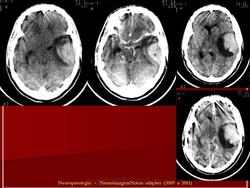

ГМ. Примитивная нейроэктодермальная опухоль (ПНЭО). +

Примитивная нейроэктодермальная опухоль (ПНЭО)